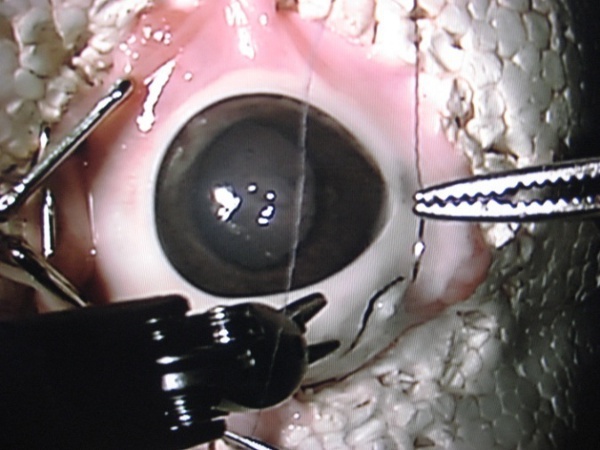

在观念上,白内障手术是相当简单,但实际上是极为精细。为了做到这一点,外科医生必须在眼睛的晶体上切开一个小孔,清除模糊患者视力的混浊部分,并且使用类似于永久隐形眼镜的一小片塑胶来替换它。眼睛的薄膜是相当敏感的,所以这项手术最可能的并发症是外科医生刺穿晶体的背部,造成视觉模糊。

为了解决这个问题,剑桥顾问(Cambridge Consultants)创造出Axsis。这是一个双臂、遥控操作的机器人,可以比人类外科医生更准确地在眼睛上做手术。机器人有两个钳子,可以在10毫米(0.4英寸)的空间精确移动,这大约为眼睛晶体的大小。外科医生使用两个摇桿和萤幕上的放大影像来控制机器人。后者(萤幕)的尺寸允许外科医生把机器人正确地移动到他想要进行手术的地方。